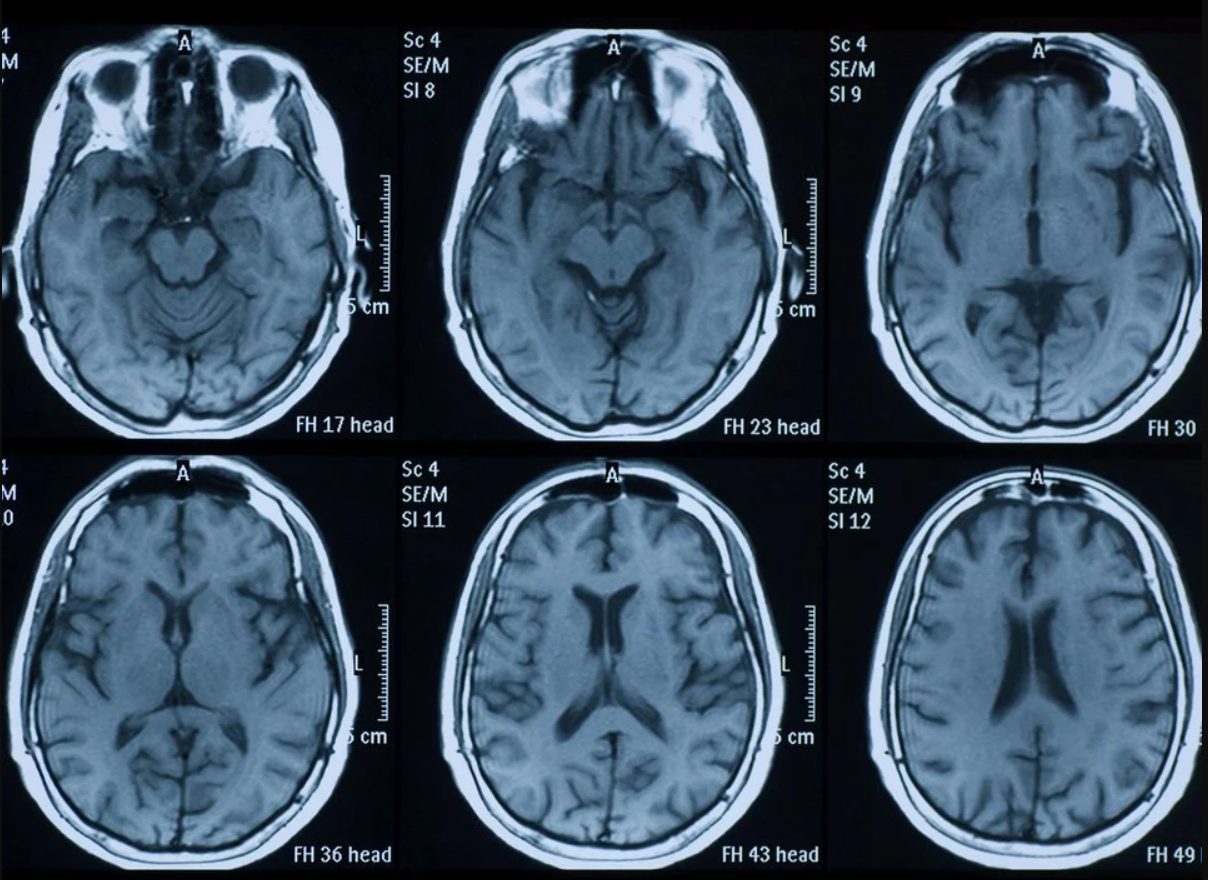

Teknolojinin sürekli gelişmesi ile herhangi bir cerrahi müdahale olmaksızın beyin ile ilgili veriler elde edilebiliyor. Hemen hemen herkes tarafından duyulan

MR (manyetik rezonans görüntüleme), insan beyninde hiç kullanılmayan alan olmadığını rahatlıkla gösterebilir. Başka bir tıbbi veriye göre, beynin %10'unu kullanıyor olsaydık, bitkisel hayatta olacağımızı söylüyor.Başka bir basit denklem aslında bu söylentinin ne kadar saçma olduğunu gösteriyor. Hepimizin bildiği gibi, insan vücudu tarafından üretilen enerjinin yaklaşık %20'si beyni eğitmek için kullanılır. Sadece %10 aktif olan organlar için bu enerji harcaması çok yüksektir. İşte bu yüzden beynimizin %10'unu kullandığımız fikrine artık basitçe efsane deniyor. Dolayısıyla insan beyninin %100 kullanıldığı gerçeği artık ispatlandı.